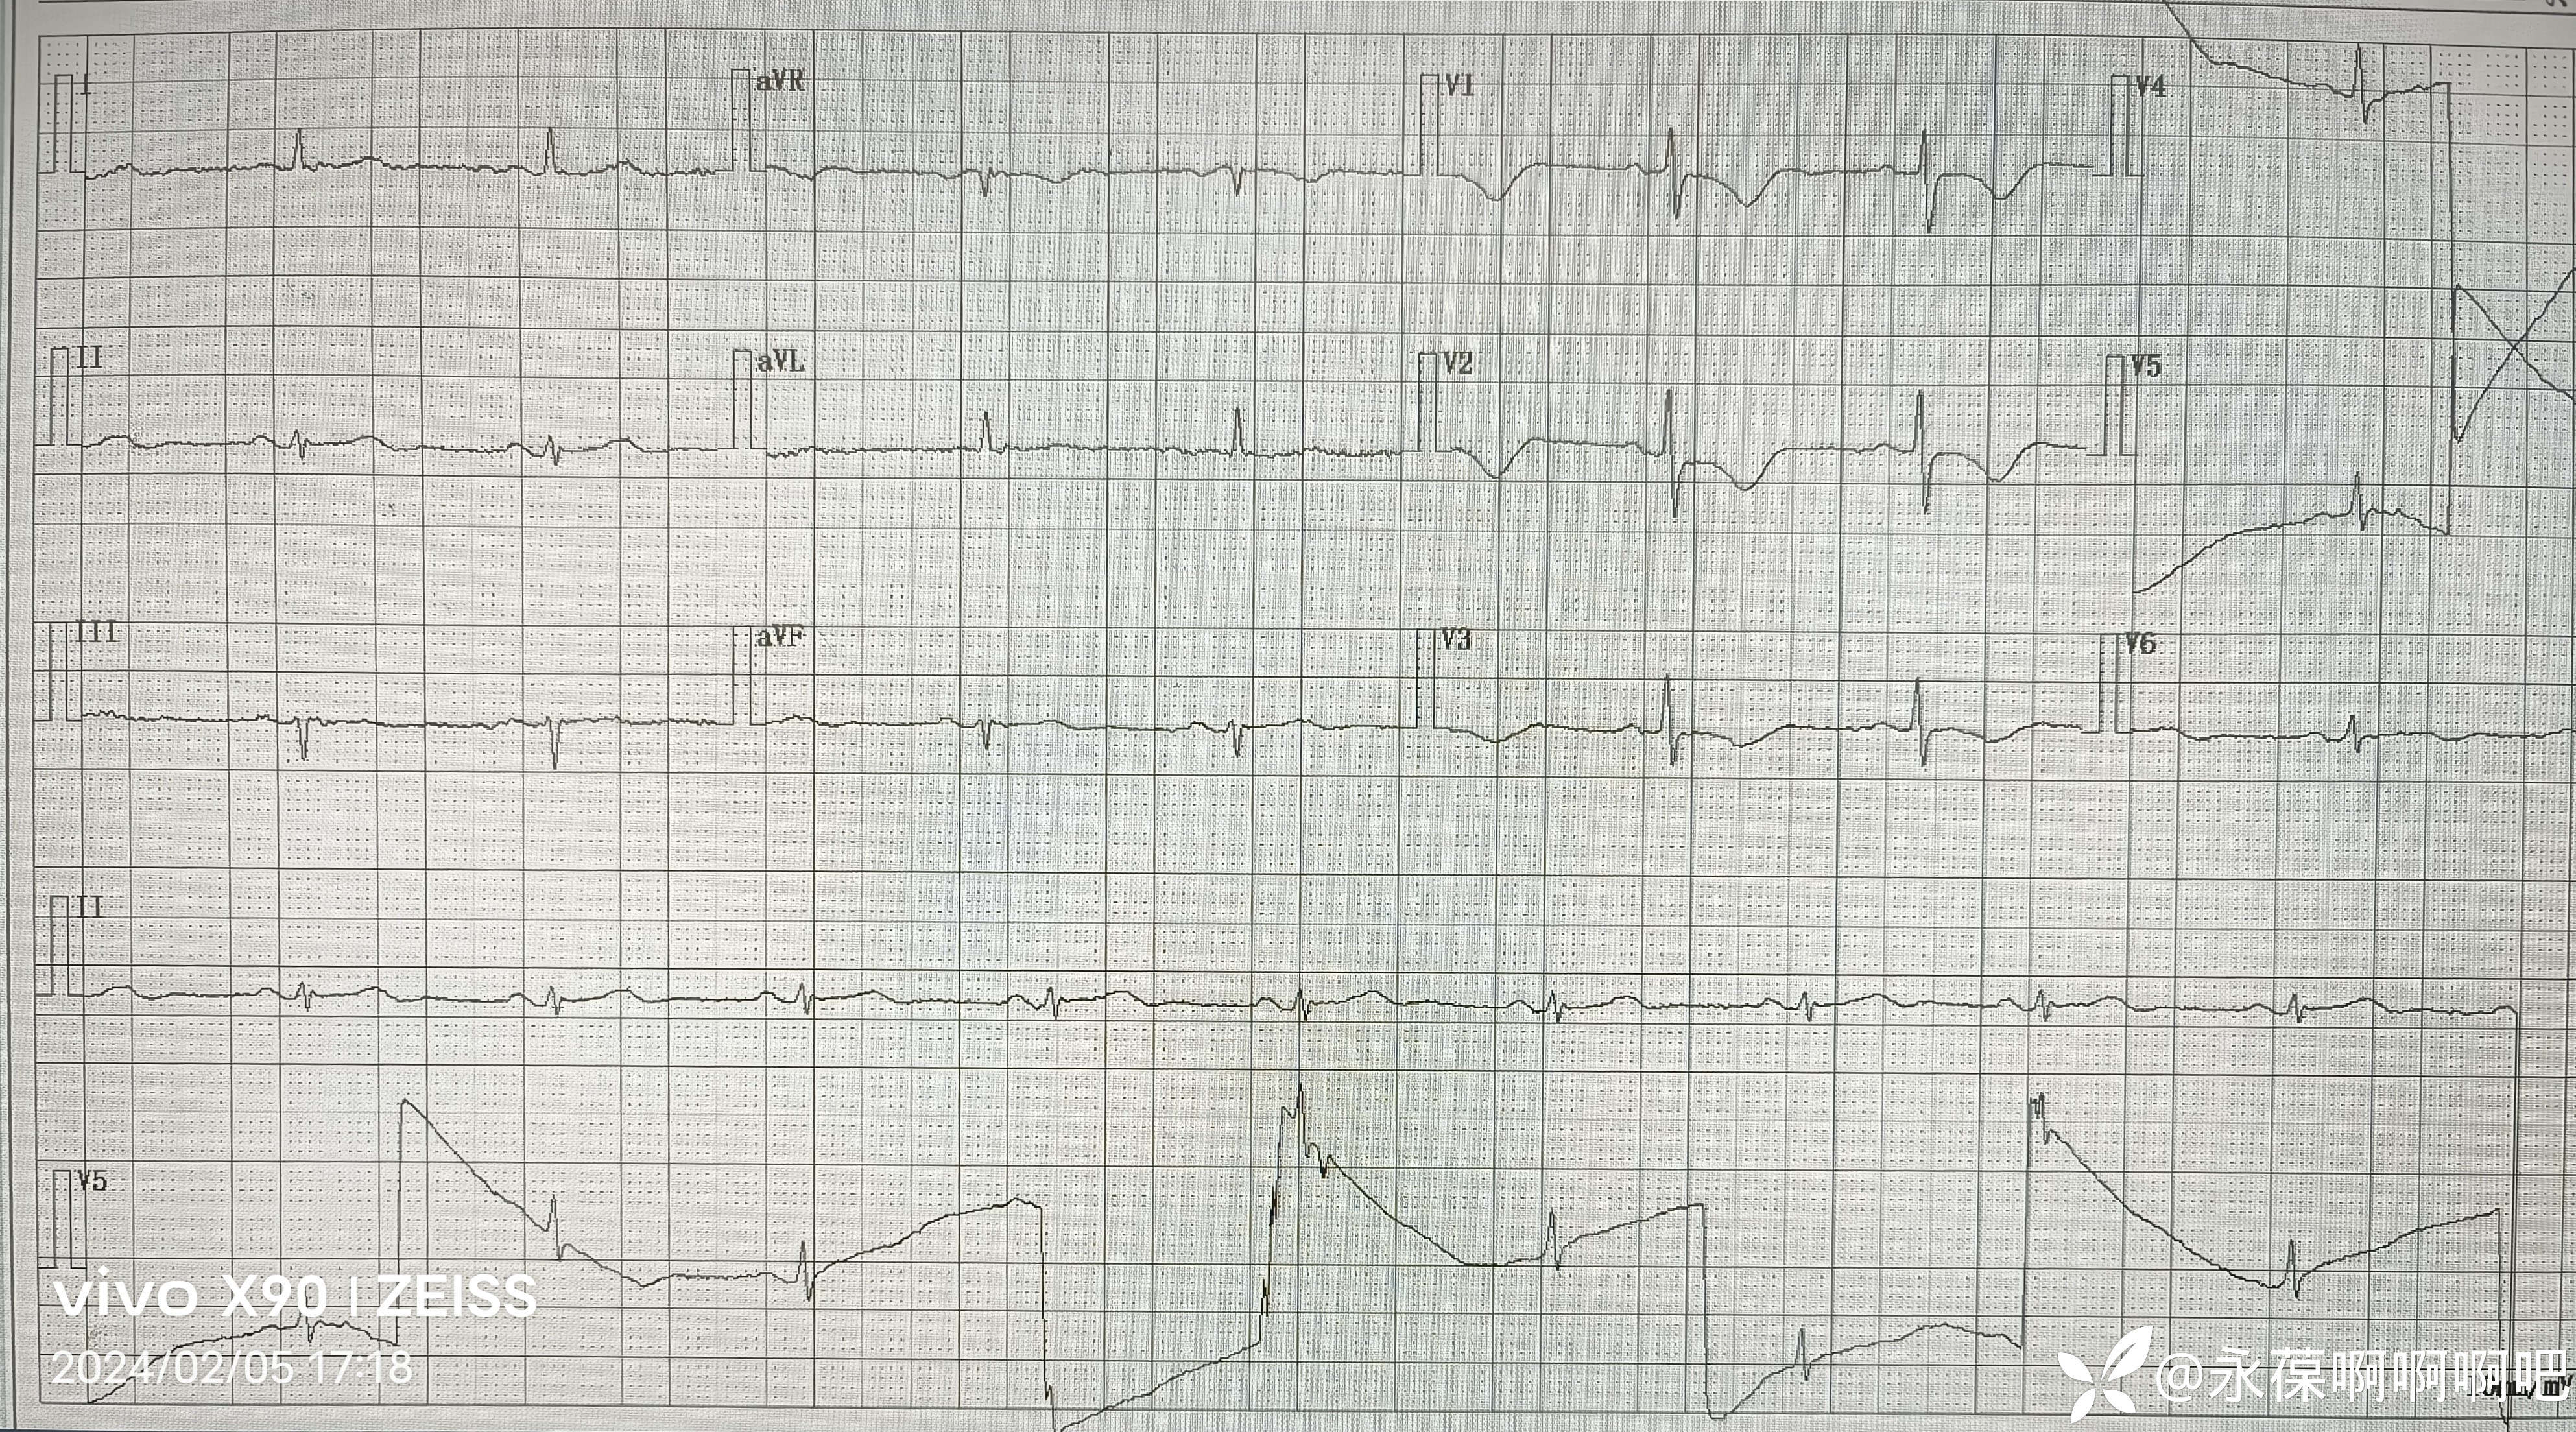

患者于入院第四天12时,排便困难,使劲憋死排便后出现血压、心率进行性下降。最低时血压66/42mmHg,心率42次/分。查体:神志恍惚,嗜睡状态,面色苍白,口唇无发绀,全身皮肤湿冷。四肢关节活动可。

即刻给予补液治疗,复查血糖7mmol/L,血常规正常,血钾 3.31mmol/L。复查心电图如下:

经补液治疗后患者血压、心率逐渐恢复正常,问答切题,四肢活动良好。